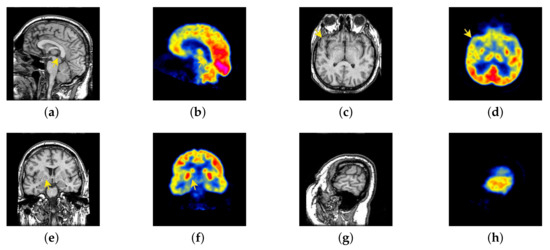

In this section, all FDG images are derived from the normal human brain, but the angle is chosen differently in Figure 24. In Figure 25, Figure 26, Figure 27 and Figure 28, we find that the color information obtained by the image fusion method based on NSCT, DTCWT, and LPSR is better preserved, but the structure information is lost more. The fusion image based on GFF, IGM, and FusionCNN method retains the complete structure information in the MRI image, but the color obtained from the FDG image is distorted. The image color information obtained by DDcGAN fusion method is too bright, resulting in unclear color area details and low contrast of color region. In contrast, the image obtained by our algorithm has moderate brightness of color information, complete structure information, and complete biological detail information.

Figure 25.

Fused medical images obtained by different algorithms (Figure 24a,b): (a) DTCWT, (b) GFF, (c) NSCT, (d) LPSR, (e) IGM, (f) FusionCNN, (g) DDcGAN, and (h) FusionNet.

Figure 26.

Fused medical images obtained by different algorithms (Figure 24c,d): (a) DTCWT, (b) GFF, (c) NSCT, (d) LPSR, (e) IGM, (f) FusionCNN, (g) DDcGAN, and (h) FusionNet.

Figure 27.

Fused medical images obtained by different algorithms (Figure 24e,f): (a) DTCWT, (b) GFF, (c) NSCT, (d) LPSR, (e) IGM, (f) FusionCNN, (g) DDcGAN, and (h) FusionNet.

Figure 28.

Fused medical images obtained by different algorithms (Figure 24g,h): (a) DTCWT, (b) GFF, (c) NSCT, (d) LPSR, (e) IGM, (f) FusionCNN, (g) DDcGAN, and (h) FusionNet.